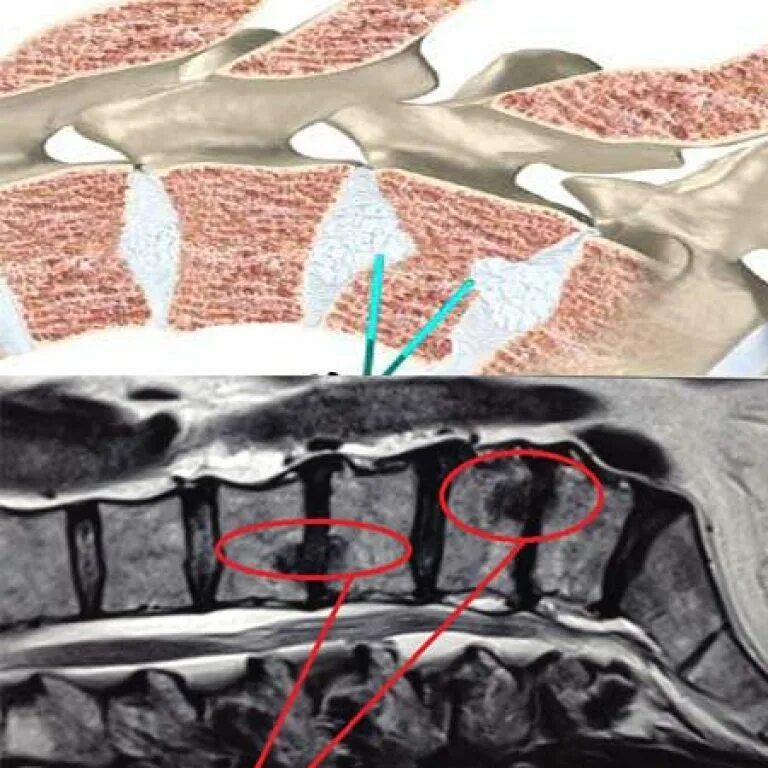

Протрузии шморля